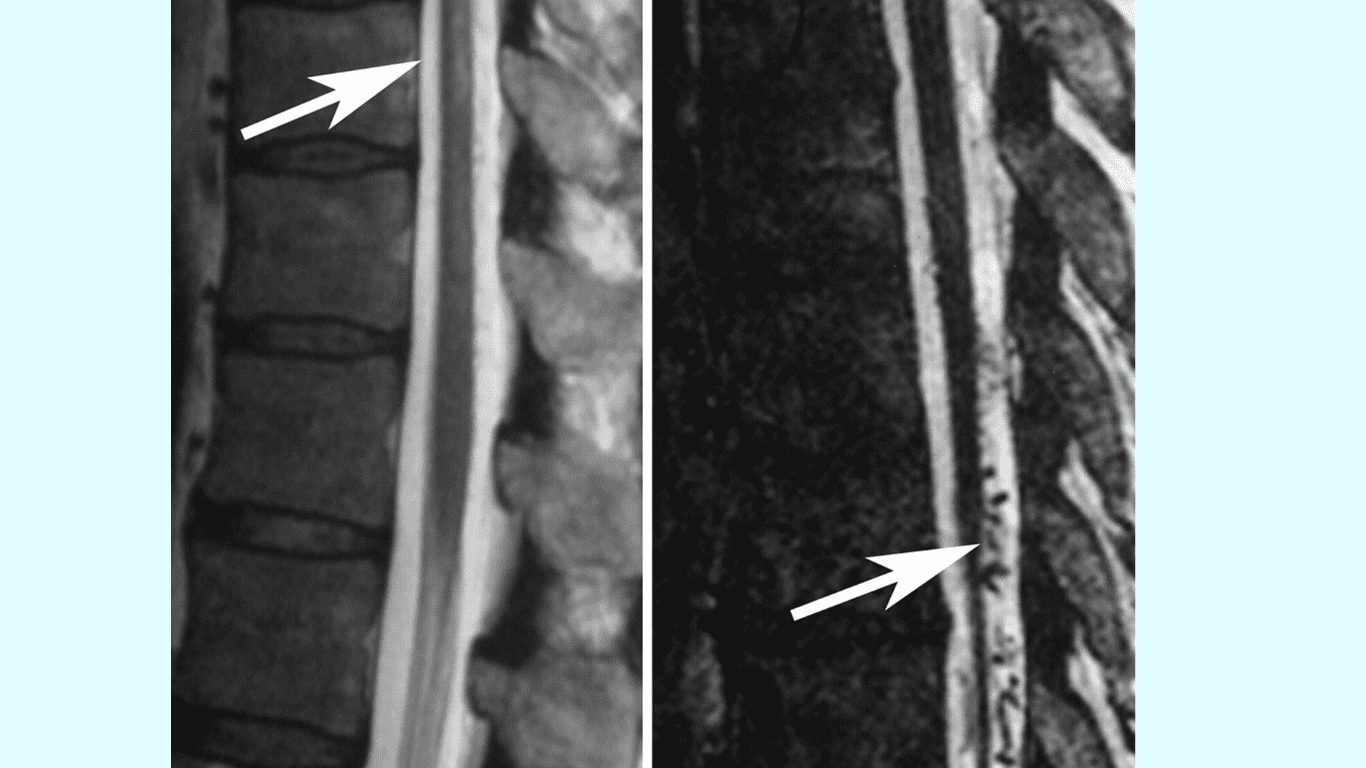

Spinal Dural Arteriovenous Fistula (SDAVF) is a rare vascular condition that affects the spinal cord.